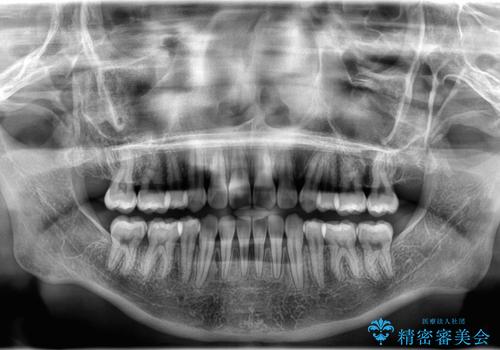

【埋伏歯】犬歯の牽引を行った矯正歯科治療

- 八重歯を主訴に来院されました。

左側犬歯が埋伏していましたが、第一小臼歯(4番目の歯)を抜歯したことでできたスペースに牽引し、右側の飛び出した八重歯を含め、歯全体を整列することができ患者様も満足していただきました。

犬歯牽引を行うかはCTを撮影し判断を行なっています。